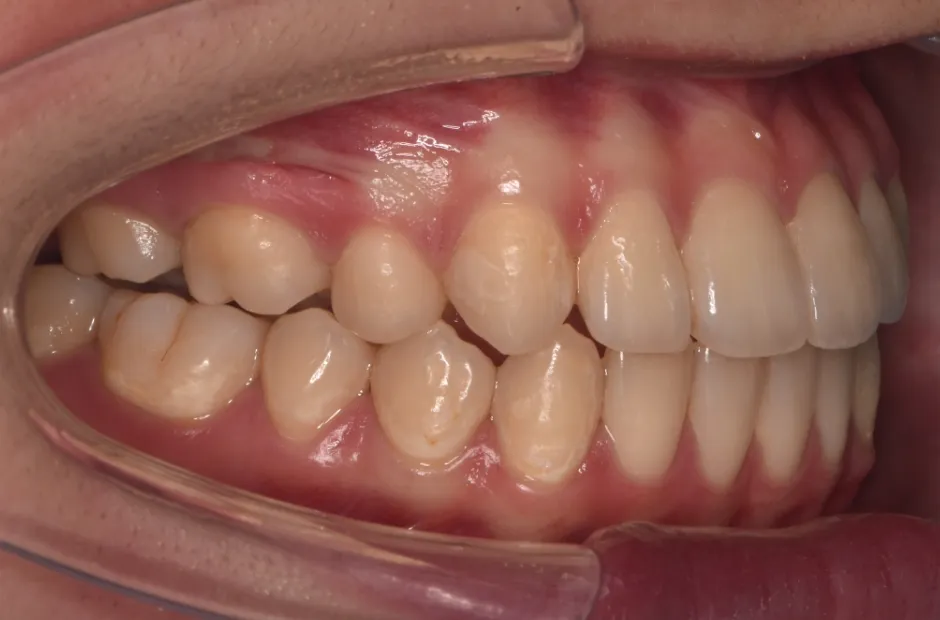

反対咬合

| 診断名・主訴 | 下顎前突、叢生 |

|---|---|

| 年齢・性別 | 23歳・女性 |

| 治療期間・回数 | 3年 |

| 治療に用いた主な装置 | 上顎5,5 下顎4,4 |

| 抜歯部位 | 舌側矯正 |

| 治療費 | 100万円(税抜) |

| リスク・副作用 | 装置による違和感・疼痛・歯肉退縮・歯根吸収・虫歯のリスクなど |

治療前

治療中

治療後